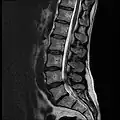

MRI

-

MRI lumbar spine with degeneration (sagittal T2 FRFSE) -

MRI lumbar spine with degeneration (sagittal T1 FSE) -

MRI lumbar spine with degeneration (sagittal FAST STIR) -